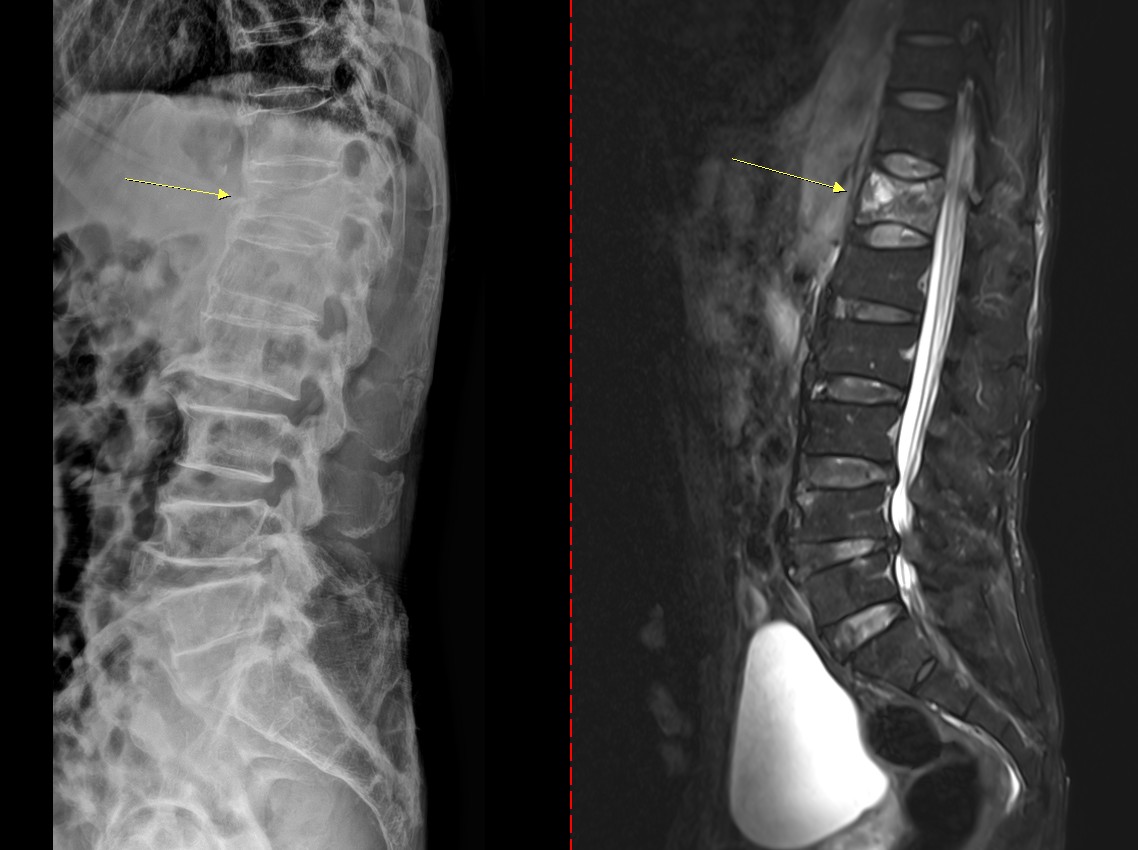

골다공증성 압박골절 환자의 척추 엑스레이(왼쪽) 와 MRI(오른쪽). (사진= 고려대안산병원 제공)골다공증은 '골다공'이라는 말 그대로 뼛속에 구멍이 생기는 질환이다. 뼛속에 구멍…